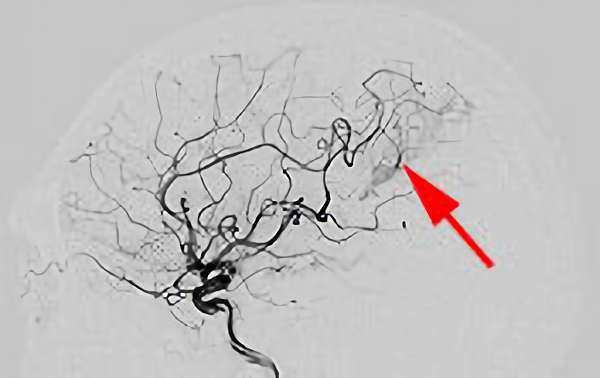

'25年10月

脳動静脈奇形

50代

大阪府の病院

No.1585 手術前

No.1585 手術中

No.1585 手術後